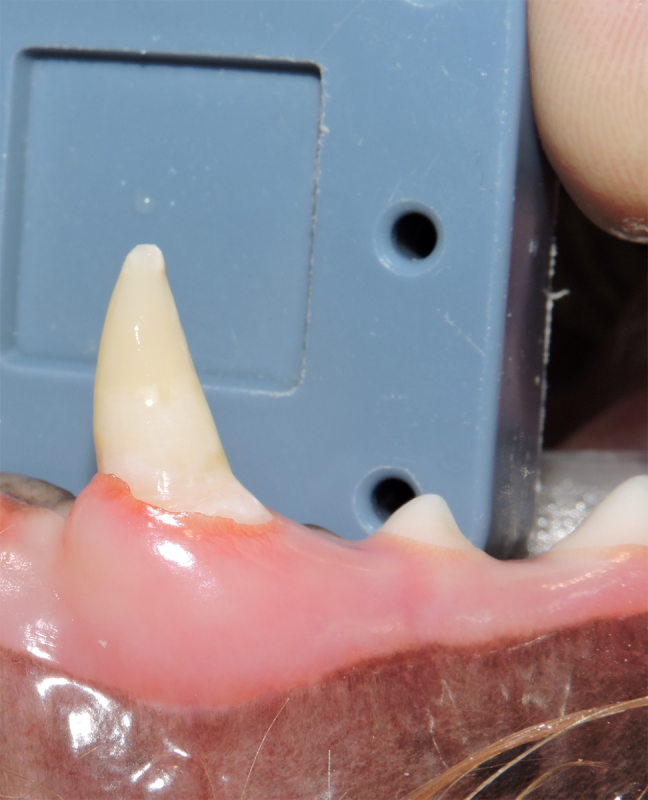

Surgical Extraction of Diseased Teeth

Periodontal disease is extremely common in dogs and cats. Over 80% of dogs and cats over two years of age have some degree of periodontal disease. Periodontal disease is best prevented by yearly professional dental cleanings starting at two years of age and at home brushing at least three times weekly. Brushing should begin at a very early age to allow your new pet to get used to regular brushing. In severe cases of infection or periodontal disease, the teeth may need to be surgically extracted. Extractions should always involve x-rays of the tooth first, as many teeth have multiple roots or may be diseased below where the eye can see. Extracting larger teeth in animals requires oral surgery, equivalent to removing wisdom teeth in people. It is vital that all of the tooth and roots be removed for the periodontal infection to resolve. In cases of important teeth with mild to moderate periodontal disease, multiple periodontal treatments can be offered to help save these teeth.

Challenging Extractions

Sometimes teeth can be quite a challenge to remove. We routinely perform difficult extractions due to abnormally formed teeth, impacted teeth, extractions from weakened bone, and retained roots, Sometimes during a routine extraction a root can get pushed into the mandibular canal or the nasal cavity, and if that happens, we are here to get it out!